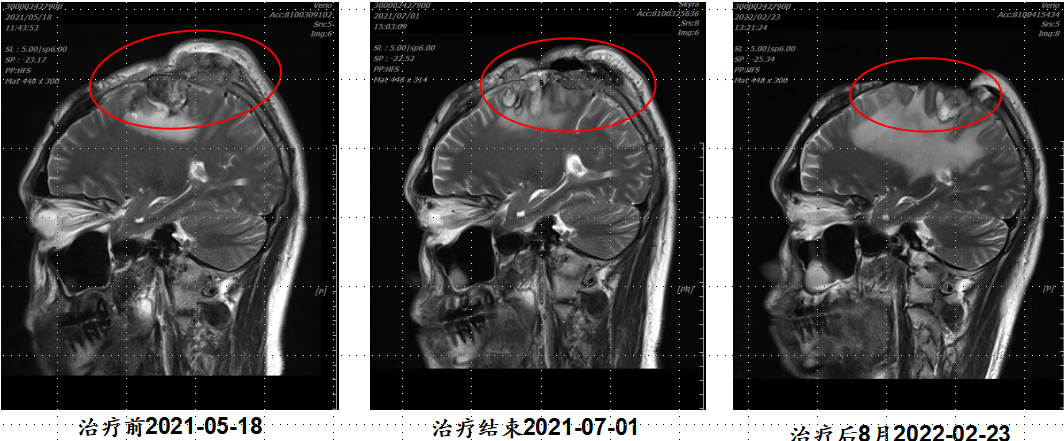

病例2:31岁脑部肉瘤术后复发,治疗7次即结痂

· 诊断:脑未分化多形性肉瘤,手术后头皮复发

· 难治点:肉瘤对常规放疗极不敏感,生长迅速

· 重(碳)离子治疗:治疗7次即见肿瘤退缩、结痂;12次结束

· 结果:治疗后9个月复查,无复发,头皮愈合良好

点评:难治性的肉瘤对重(碳)离子也特别敏感,治疗期间即可见肿瘤肉眼可见的消退。

【病例提供医生:王馨 科室:放疗中心一科】